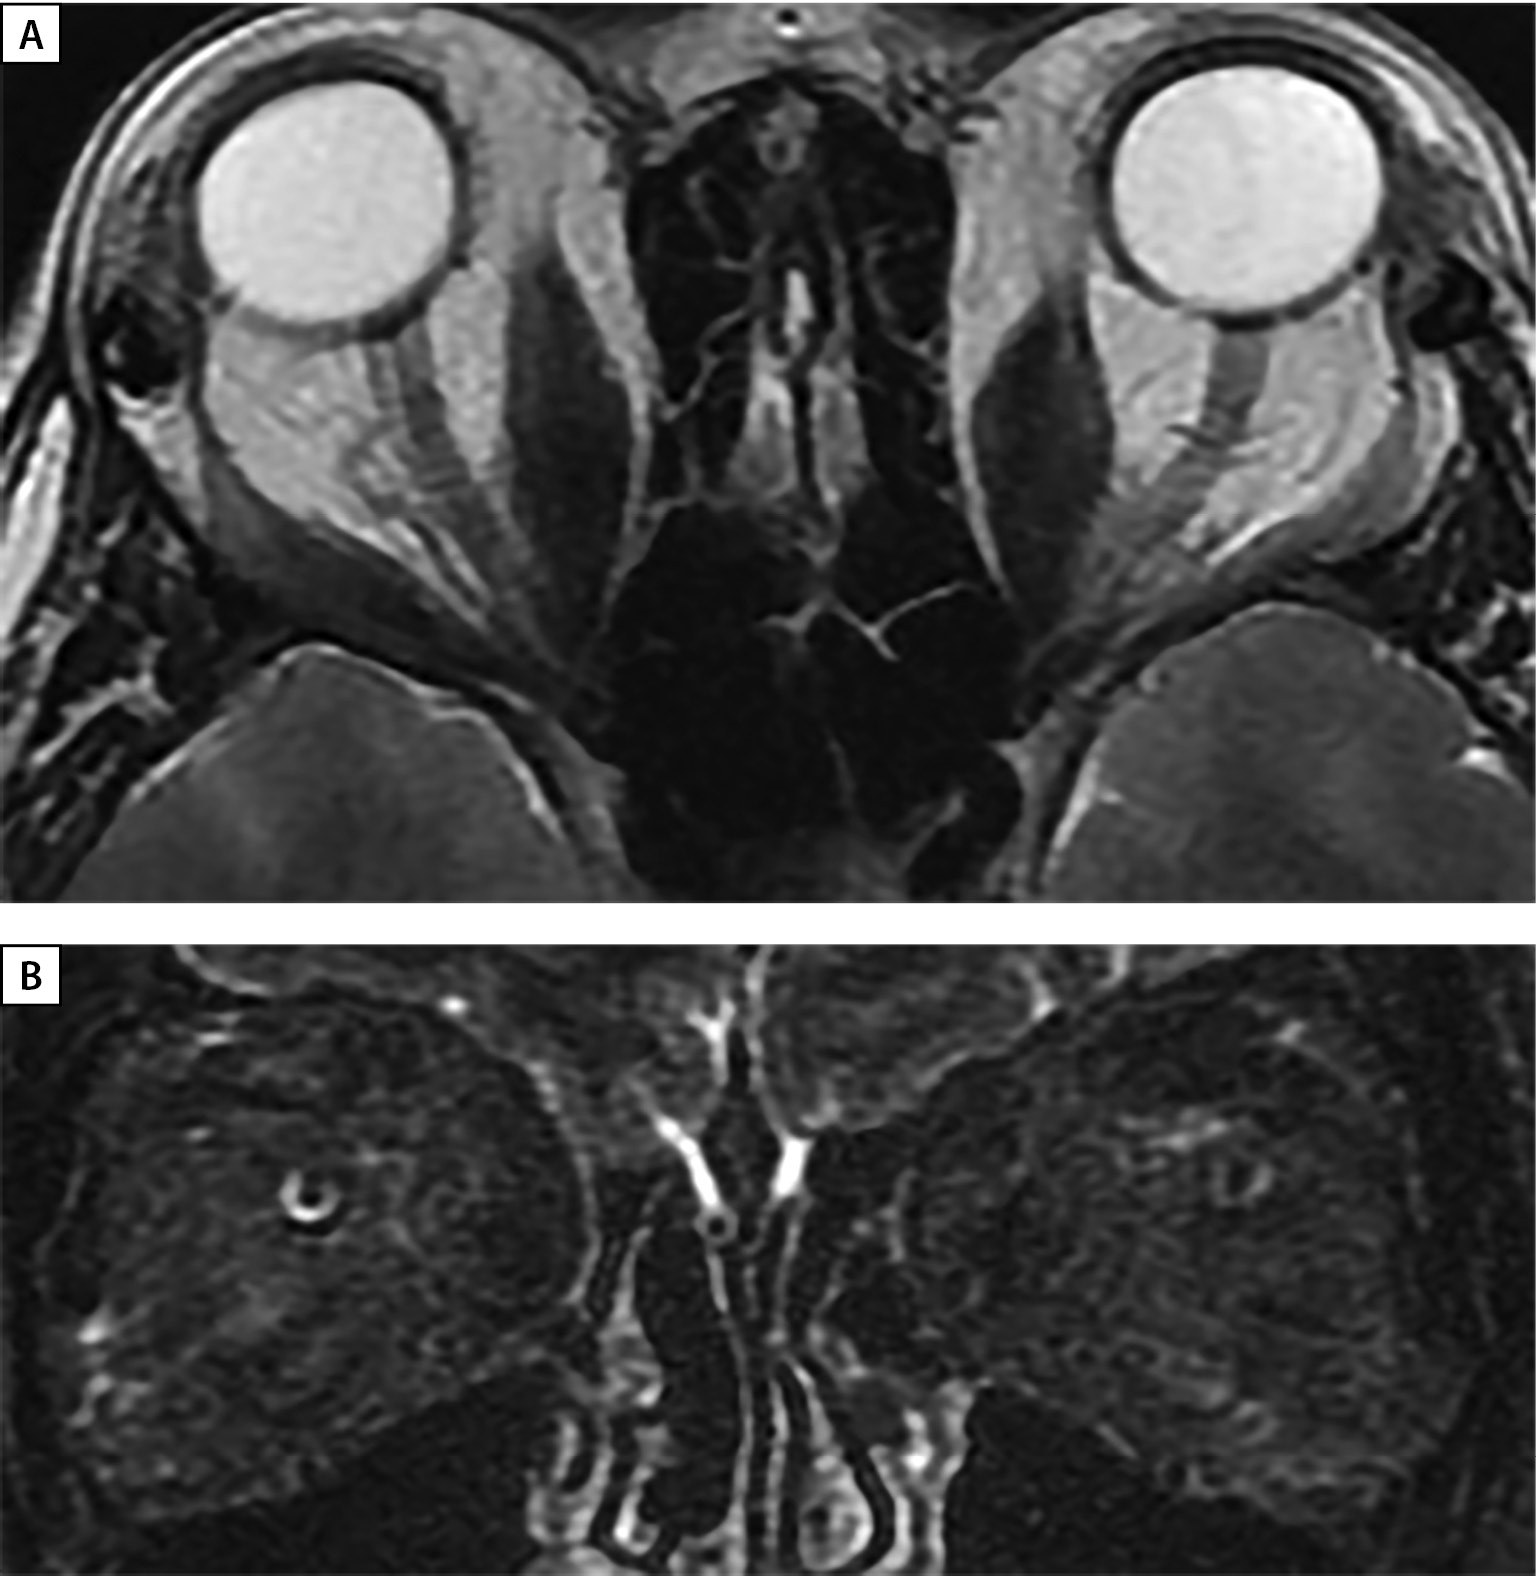

По данным МРТ орбит: без существенной динамики по сравнению с МРТ от 11.12.2020 г. (рис. 2 А, В, С). По заключению офтальмолога: ЭОП тяжелой степени, активная фаза (CAS=4); двусторонняя ОН; частичная офтальмоплегия; ретракция век; хемоз; лагофтальм. Острота зрения: правый глаз=0,4, левый глаз=0,6. С учетом сохраняющейся активности ЭОП и прогрессирующего снижения зрительных функций продолжена пульс-терапия ГК (суммарная доза метилпреднизолона 5750 мг + преднизолона 1800 мг). На этом фоне достигнут положительный эффект — улучшение подвижности глаз и уменьшение отека век. Однако, по данным компьютерной периметрии (Humphrey 30-2), сохранялись зрительные расстройства: правый глаз — диффузное снижение контрастной светочувствительности, множественные абсолютные скотомы в нижней половине, относительные скотомы в верхней половине, левый глаз — диффузное снижение контрастной светочувствительности, множественные относительные скотомы, в связи с чем пациентка была направлена на консультацию в ФГБНУ НИИ ГБ им. Краснова для решения вопроса о хирургическом лечении ЭОП (декомпрессии орбит).

Рисунок 2. МРТ орбит (А — аксиальная; В, С — корональная проекции) до лечения:

выраженное утолщение верхних, нижних, медиальных прямых мышц, апикальный синдром.

С — режим Т2 STIR c жироподавлением — выраженный отек всех ЭОМ.